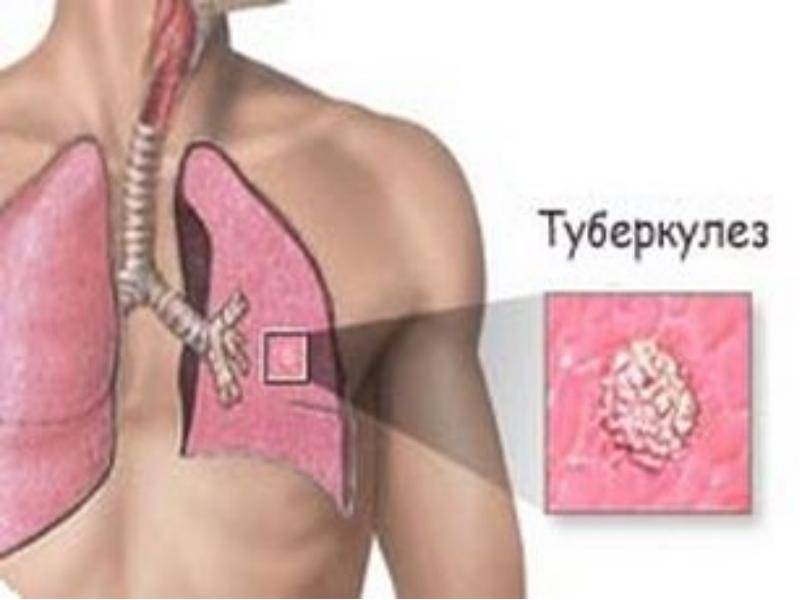

Симптомы и признаки туберкулеза: как распознать заболевание